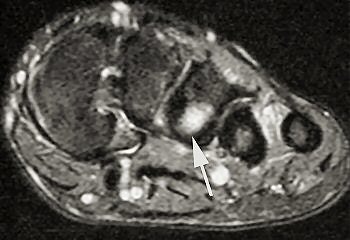

| Short axis image shows bone marrow edema at the base of the third metatarsal. |

The follow-up study was led by Dr. Nancy Major, associate professor of radiology at Duke University Medical Center's musculoskeletal division. Her study determined that MRI can effectively predict metatarsal stress fractures by depicting bone marrow edema (a precursor to fractures), thereby enabling the prevention of potential fractures with the use of orthotics.

In this study, 26 male basketball players from Duke and North Carolina Central University in Durham were imaged before and after their 2003 season. Although 19 of 52 feet showed abnormalities with MRI, only one player had complaints of a symptomatic midfoot. The use of an orthotic provided immediate relief, and the player did not subsequently develop stress fractures.

A player experiencing no symptoms, however, did develop a metatarsal stress fracture before he could be fitted for an orthotic ("The role of imaging in the feet in asymptomatic collegiate basketball players," RSNA meeting, December 2, 2004).